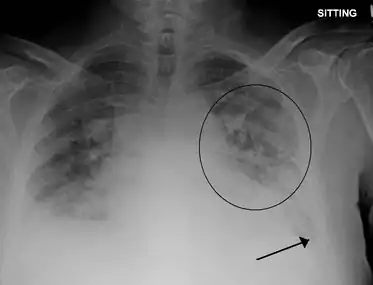

| Pulmonary edema with small pleural effusions on both sides. | |

Low oxygen saturation and disturbed arterial blood gas readings support the proposed diagnosis by suggesting a pulmonary shunt. A chest X-ray will show fluid in the alveolar walls, Kerley B lines, increased vascular shadowing in a classical batwing peri-hilum pattern, upper lobe diversion (increased blood flow to the superior parts of the lung), and possibly pleural effusions. In contrast, patchy alveolar infiltrates are more typically associated with noncardiogenic edema[8]

Acute pulmonary edema